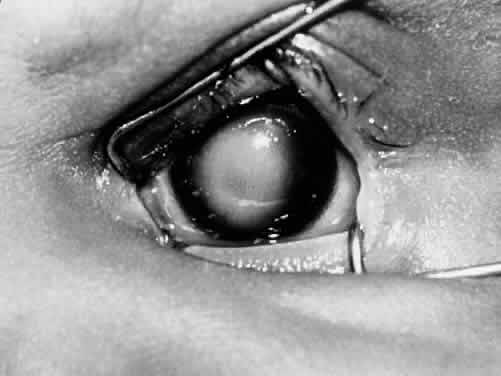

Microphthalmos with cyst results from proliferation of neuroectoderm at the edge of a persistent embryonic fissure. The cavity of the cyst is continuous with the interior of the microphthalmic globe.2,46 Rudimentary optic nerve fibers can be seen within the cyst wall.47 The microphthalmic eye itself is often overshadowed by the larger orbital cyst (Fig. 5).48 Cases of extreme microphthalmos may be confused with anophthalmia.49,50 The anterior segment of the microphthalmic eye may appear normal, although it commonly displays marked disorganization and iridocorneal adhesions. The lens is frequently cataractous and dislocated.51 The retina is usually detached, disorganized, and gliotic.52 No consistent -association has been documented between mi-crophthalmos with cyst and a specific systemic anomaly. Systemic disorders reported with microphthalmos with cyst include central nervous -system defects (e.g., meningoencephalocele, hydrocephalus) and cardiac, urogenital, facial, and skeletal abnormalities.53–55

Fig. 5. The structure visible on the right side is the cyst component of microphthalmos with cyst. (AFIP #220948; courtesy of Torrence A. Makley, Jr, MD)